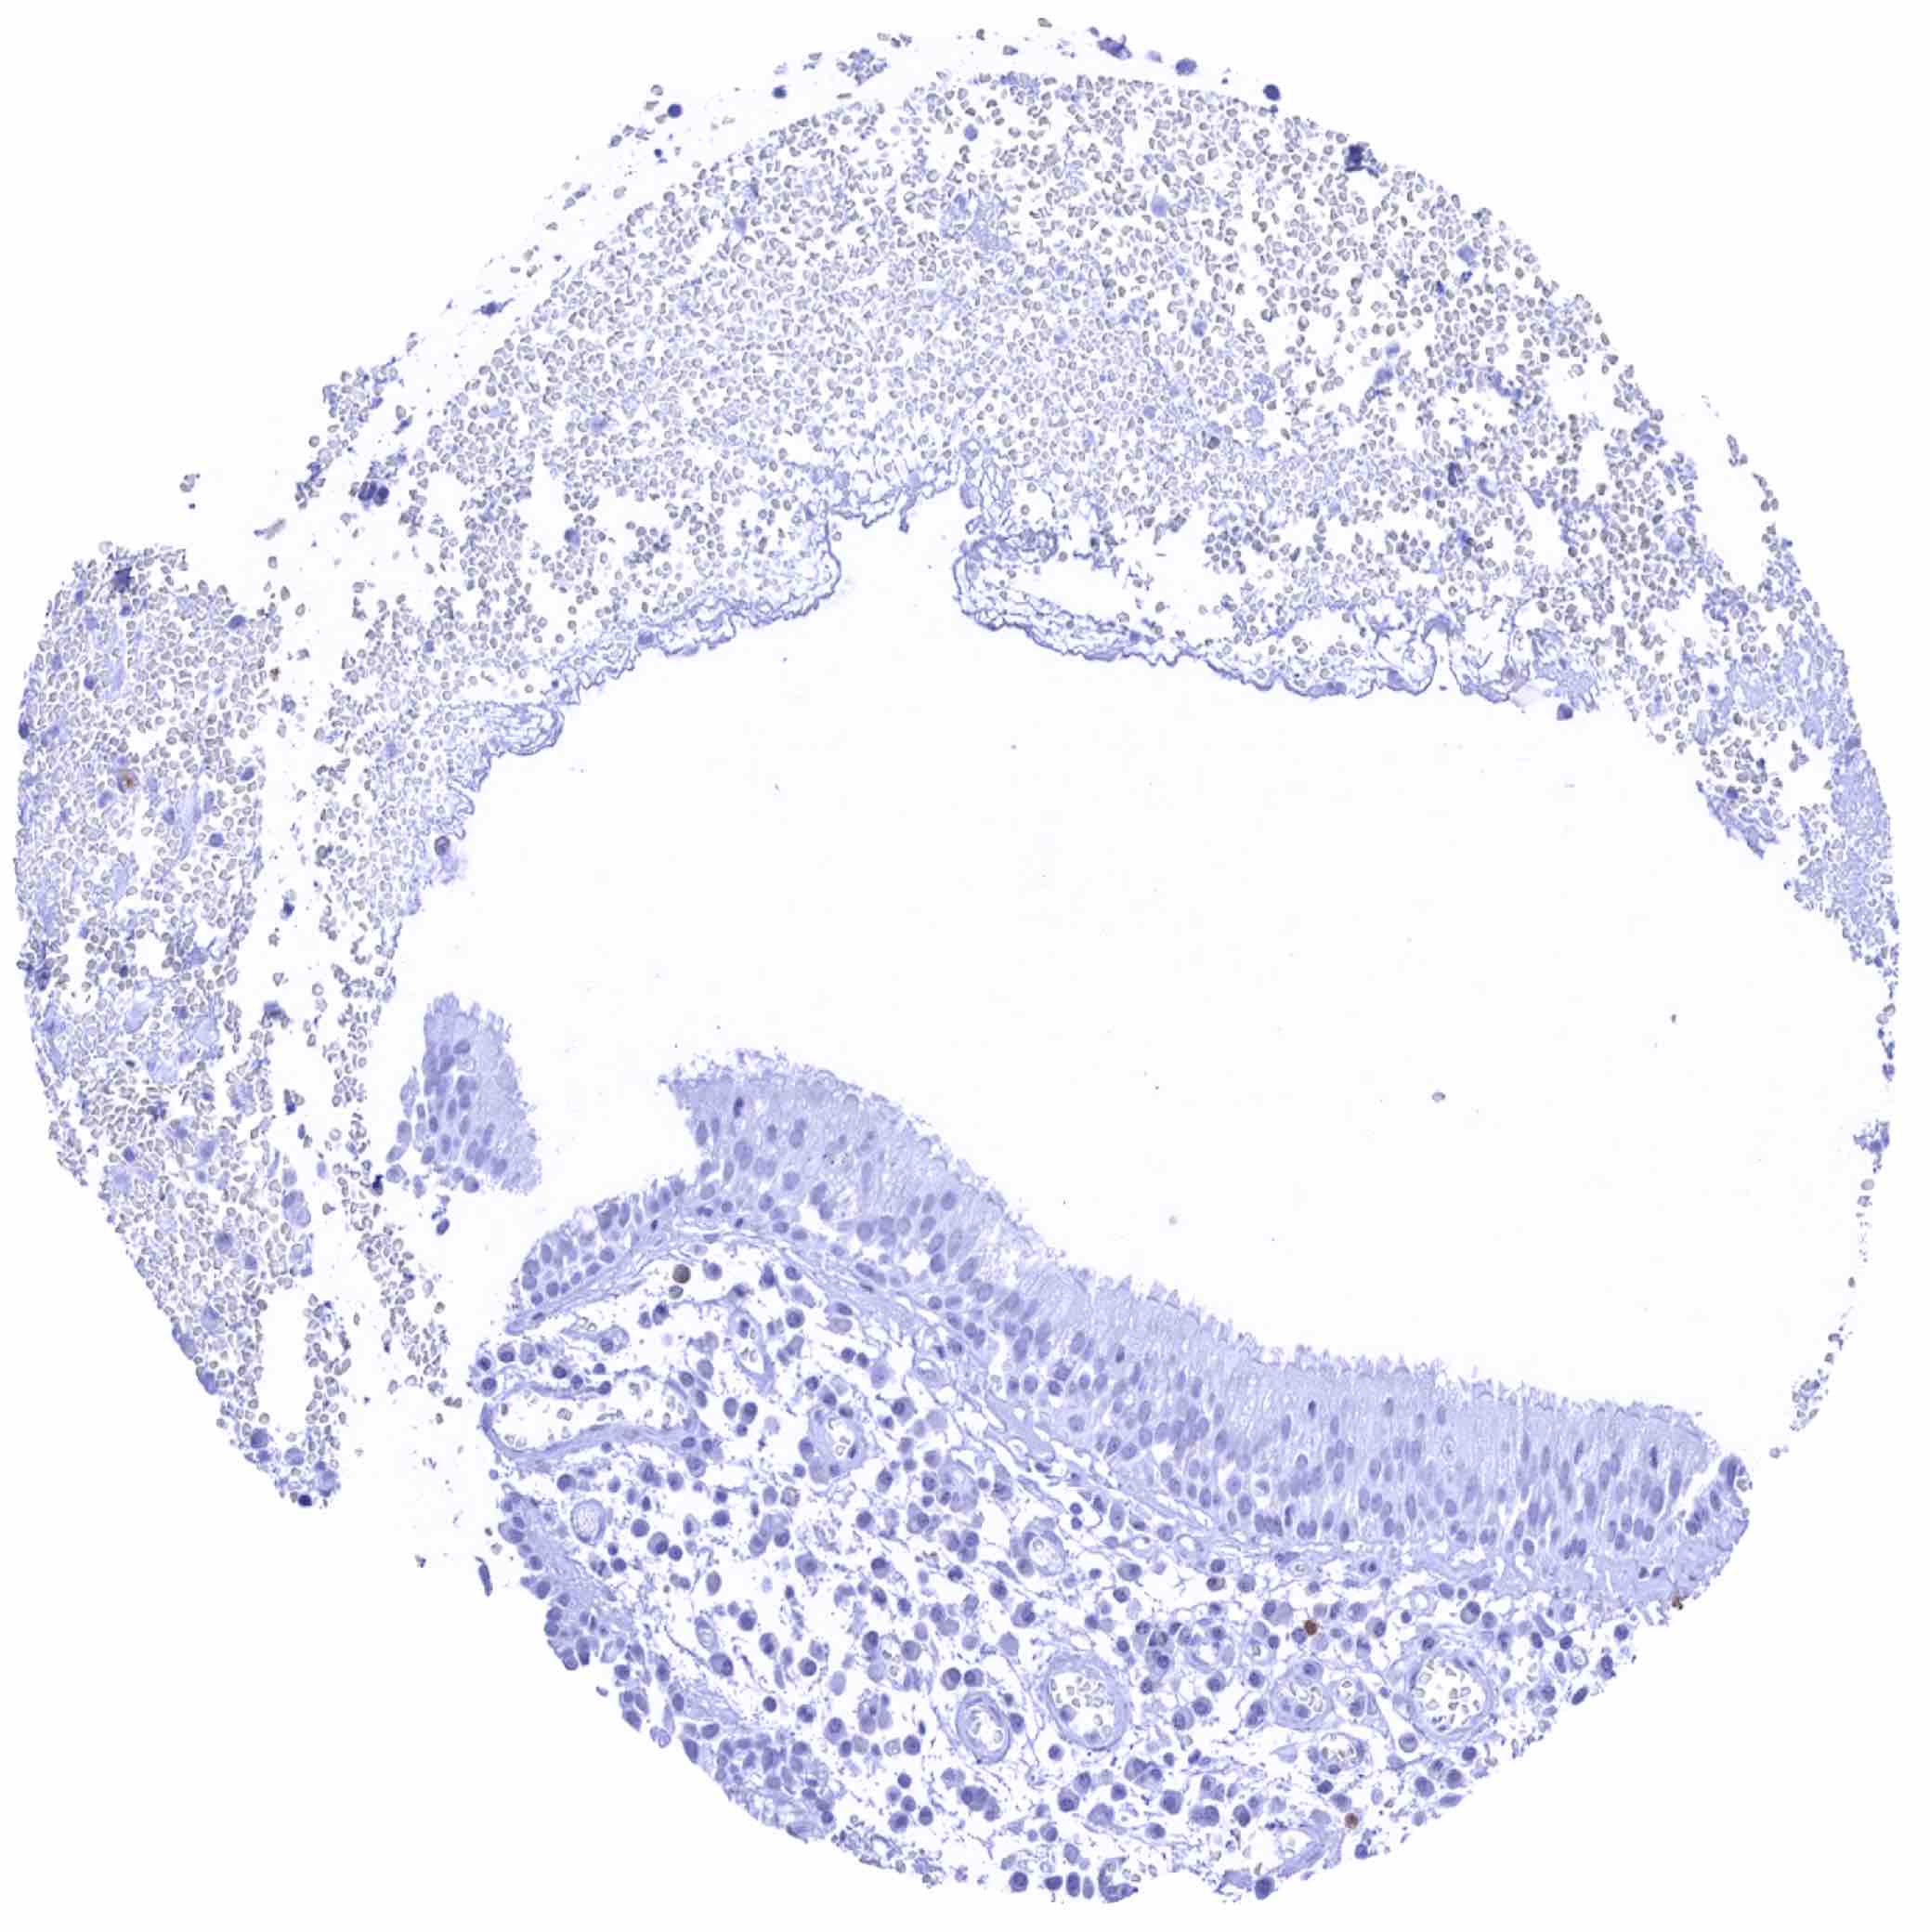

Tonsil – Variable, moderate to strong, nuclear and cytoplasmic TYMS staining of a fraction of lymphocytes, especially in a germinal centre.

Tonsil – Variable, moderate to strong, nuclear and cytoplasmic TYMS staining of a fraction of lymphocytes, especially in a germinal centre

Tonsil, surface epithelium – Weak to moderate, predominantly nuclear TYMS staining of a subset of suprabasal squamous epithelial cells